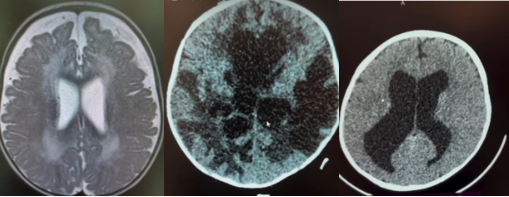

Мы уточняем тип гидроцефалии (внутренняя / наружная) и исключаем окклюзионную форму с помощью нейровизуализации (МРТ/КТ — по показаниям) и консультации нейрохирурга.

Виды гидроцефалии

Ликвор не может пройти по своим путям из-за блока: кисты, стеноза, перегородки, опухоли и т.д. Часто требует хирургического лечения: шунтирование или эндоскопическая операция (ЭТВ).

Проходимость путей сохранена, но нарушено всасывание ликвора. Решение о шунтировании зависит от симптомов и динамики.

Также называется: • доброкачественная наружная гидроцефалия младенцев • benign external hydrocephalus (BEH) • benign enlargement of subarachnoid spaces (BESS) Это увеличение субарахноидальных пространств у младенца при нормальном или слегка увеличенном размере желудочков. Причина: возрастная незрелость систем всасывания ликвора, а не питание и не внутричерепное давление. Это неопасный, временный вариант, который чаще всего проходит по мере роста ребёнка.